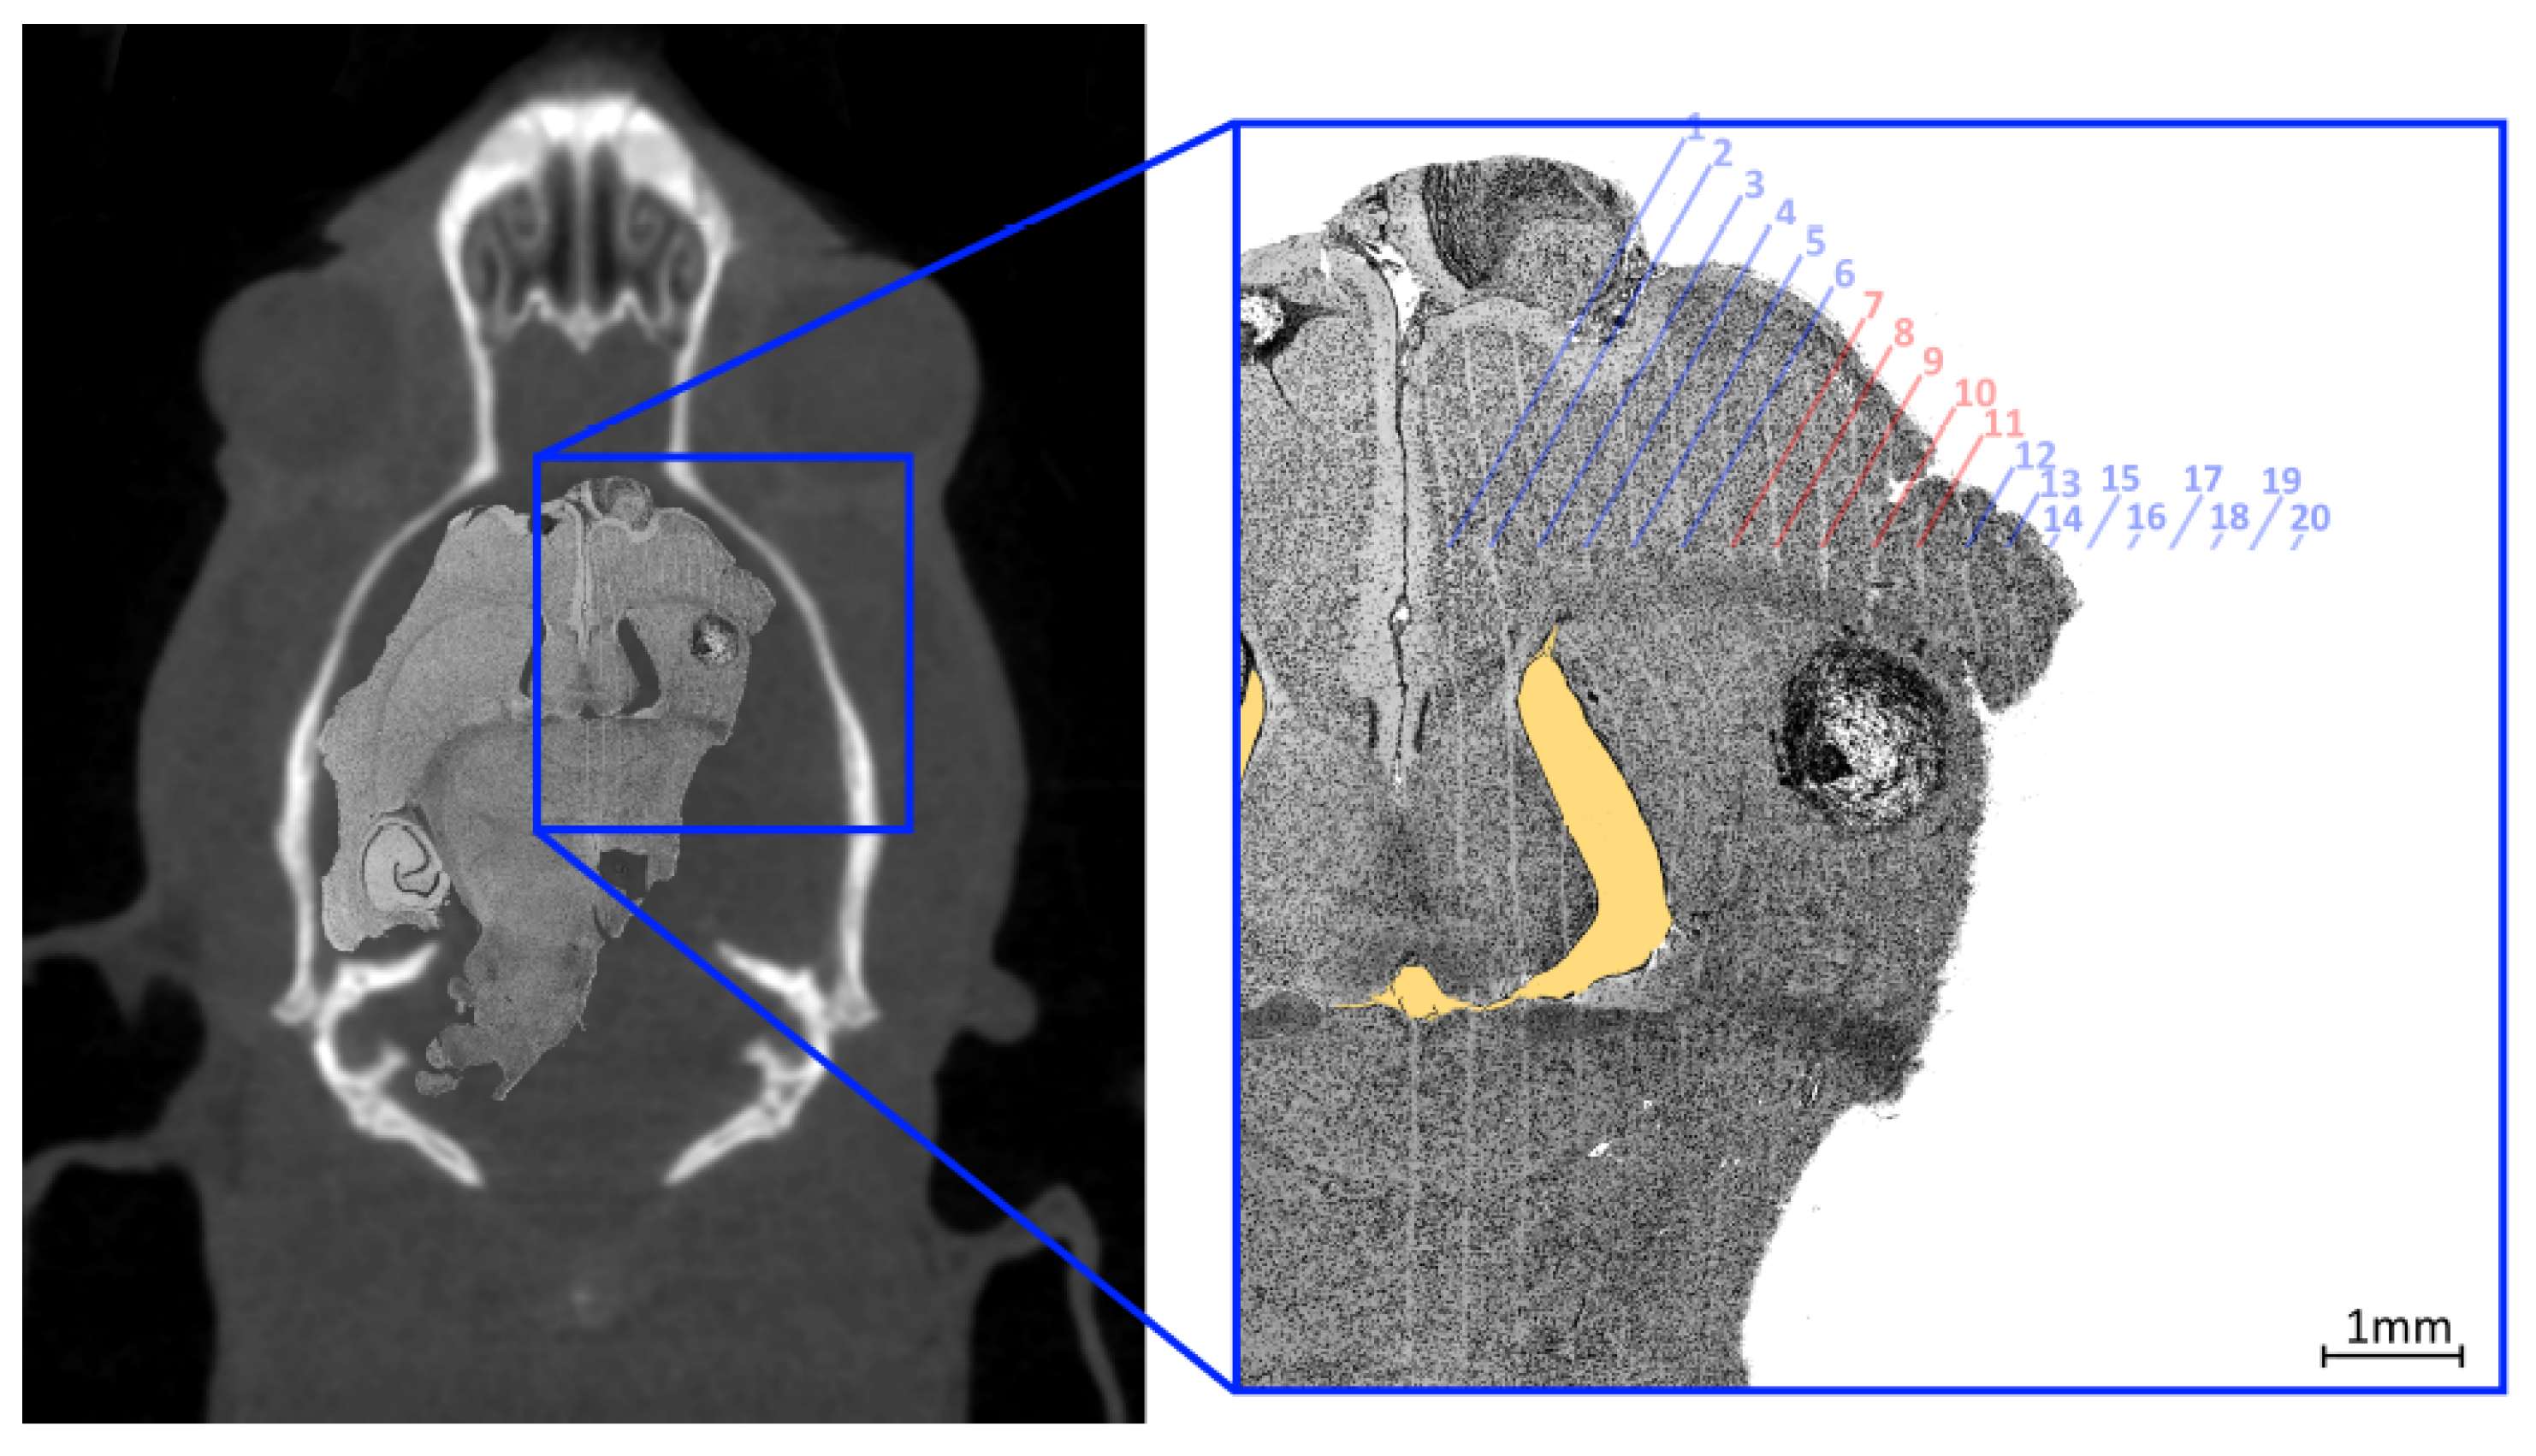

For histological analysis, a rat was euthanized with an intraperitoneal injection of lethabarb 14 days after MRT, using a 325 mg/mL solution to a dose of 800 mg/kg, according to Engels et al. [30]. The brain was collected by removing the skull and placed immediately in 10% neutral buffered formalin for fixation. Fixed brains were sliced transversely, processed through graded alcohols and xylene, embedded in paraffin, to obtain 4 μ m sections. These sections were stained with haematoxylin and eosin. Histology images were acquired using a Leica DMI4000 B Inverted Microscope using multi-step (tiled) image acquisition with light field corrections applied presented in Figure 10.

The curved appearance of some of the microbeams tracks, particularly due to towards the middle third of the treatment field is a results of physical deformation such as manual handling of the histology slice during slide preparation and dehydration of the sliced sample. The yellow shaded region highlights a void in the brain material caused by manual handling of the fragile tissue. These deformations remove the ability to accurately spatially calibrate the image however, the known field properties may be used to investigate alignment accuracy. The 8 mm × 8 mm MRT treatment field used to treat the imaged animal (bearing a 1.50   m m 3 tumour) consisted of 20 microbeams ( 50 μ m FWHM, 400 μ m pitch) the centre of such field lying between microbeams 10 and 11. The histology image shows the tumour at 7 m m depth enveloped by microbeams 7 to 11 of the treatment field; with the tumour at this depth not representative of the centre of mass targeted during treatment. Confirmation of accuracy here supports the potential reduction of the treatment field size for future work.

Figure 10. Composite image with a histology slide overlaid on corresponding coronal CT slice of tumour-bearing rat, 14 days after MRT treatment (left). The enlarged image (right) shows a tumour situated within the MRT treatment field (parallel vertical lines) with microbeams present and expected numbered with red text identifying the microbeams that transit the tumour mass (dark circular object at the centre of the frame). The yellow shaded region highlights a void in the brain material caused by manual handling of the fragile tissue.